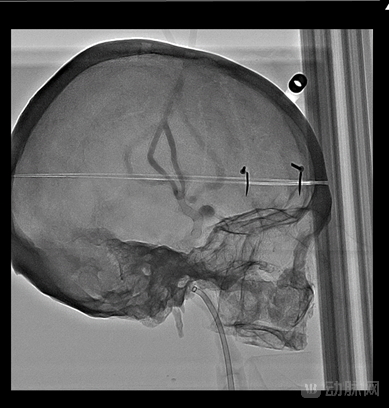

76微米显微高清 突破成像极限

Alphenix Sky+搭载全球首创显微高清探测器,像素尺寸突破性达到76微米,像素面积仅为传统探测器的1/4,空间分辨率较以往提高一倍,达到了6.6lp/mm,可以突破传统成像技术放大极限,让术者如同在显微镜下进行介入手术,洞察微小病灶,实现精准导航,结合全16bit高清影像链和Alphenix2.0智能应用等软硬件创新成果,为神经、心脏、肿瘤、外周大血管等领域的精细化复杂介入手术提供全临床显微级高清成像,增强医生手术信心。